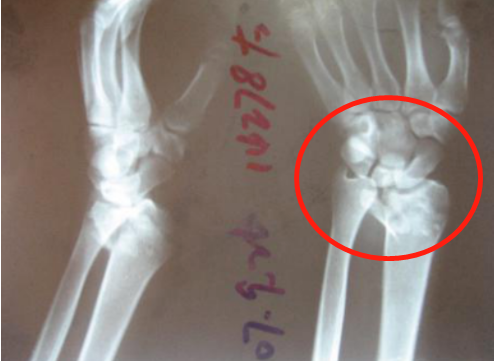

(裂纹型骨折) (移位型骨折) 实际上,“骨裂”究其本质上还是骨折,只不过骨折不移位或移位不明显罢了。换言之,骨裂是骨折的一种类型,而非与骨折相提并论,其治疗原则和其他类型骨折并无差异,都是复位、固定和功能锻炼。 其二,骨裂就是骨折,不固定或固定时间不够依然会出现移位或者骨折延迟愈合、不愈合,千万不能区别对待。说到这里,就不得不提及骨折的治疗原则——“复位、固定、功能锻炼”,虽然只有短短的7个字,却饱含了很多重要的信息。复位是骨折后首要解决的问题,这个复位根据骨折部位不同有的需要功能复位,有的需要解剖复位。总之,骨科医生治疗骨折的第一步就是复位,骨裂的患者这一步自然不用多做。 接下来要解决的问题就是固定,为什么要固定?“固定”解决的问题是复位后骨折断端的维持,所谓骨裂的患者往往骨折断端都没有明显移位,但是这并不代表骨折不会出现继发性移位,因为没有有效固定或者未按医嘱要求固定,导致不得不采取手术治疗的案例临床上也比比皆是,有的患者觉得只是骨裂就掉以轻心、麻痹大意,不遵医嘱佩戴石膏或支具,殊不知这些原则都是用血泪的教训总结出来的,目的就是同样的错误不可再犯,不要去承受这本可避免的痛。 (骨折后石膏固定) 有时候规避风险只需要一个合适的石膏,固定不牢,势必移位,移位之后再手术往往导致错过最佳的锻炼的时间,一来二去就是出现关节僵硬、骨质疏松、肌肉萎缩等这样那样的骨折并发症,而这一切也仅仅是一个石膏就可以避免的。 况且,没有骨折的患者,关节部位的韧带损伤常常也是需要石膏固定的,目的是通过“制动”促进韧带的修复。 总之,石膏固定的目的是在保护或者维持良好的复位,是加分项而非减分项,能用石膏固定解决的骨折说明骨折不算严重,预后还是很好的。 其三,“动静结合”的理念贯穿了骨折治疗的自始至终。石膏固定并非不能活动和锻炼,其固定的只是局部,没有石膏固定的其他部位可以动也鼓励多动,可以避免很多骨折并发症的发生。众所周知,石膏固定限制骨折局部的活动,非石膏固定的区域可自由活动,需注意“上肢不提物、下肢不负重”这一基本要求。 固定骨折局部的目的是为骨折愈合提供一个稳定的内环境,促使其早期纤维连接直至中后期形成内外骨痂实现骨折的愈合。在普通大众看来,带上石膏非常不方便不能洗澡;非常不好看被人嘲笑;非常不舒服不太透气。可是这些理由在我们看来是站不住脚的。 (移位后畸形手术治疗) 骨折本身就是一件麻烦的事情,如果仅仅是怕麻烦而不去石膏固定的话,那很可能会因为图省事而继发的骨折断端移位、延迟愈合、不愈合等并发症,届时增加的就是金钱和时间,而得到的结果是关节的僵硬和肌肉萎缩,细想起来极不划算,这不是人们常说的那句古话:捡个芝麻丢个西瓜,得不偿失啊! 骨折患者的幸福都是一样的而不幸却是各不相同的。在相对简单骨折的治疗中遵循原则、遵从医嘱相信科学、有效固定依然是行之有效的方法。